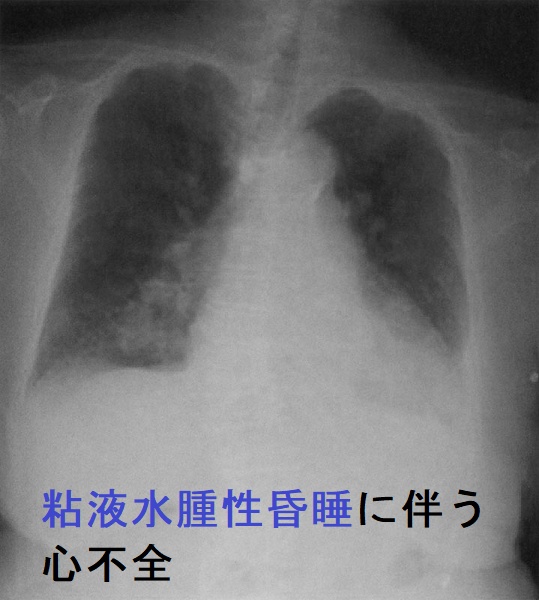

- 心不全

- 低Na(ナトリウム)血症(続発性副腎不全);低ナトリウム血症自体で低体温症に